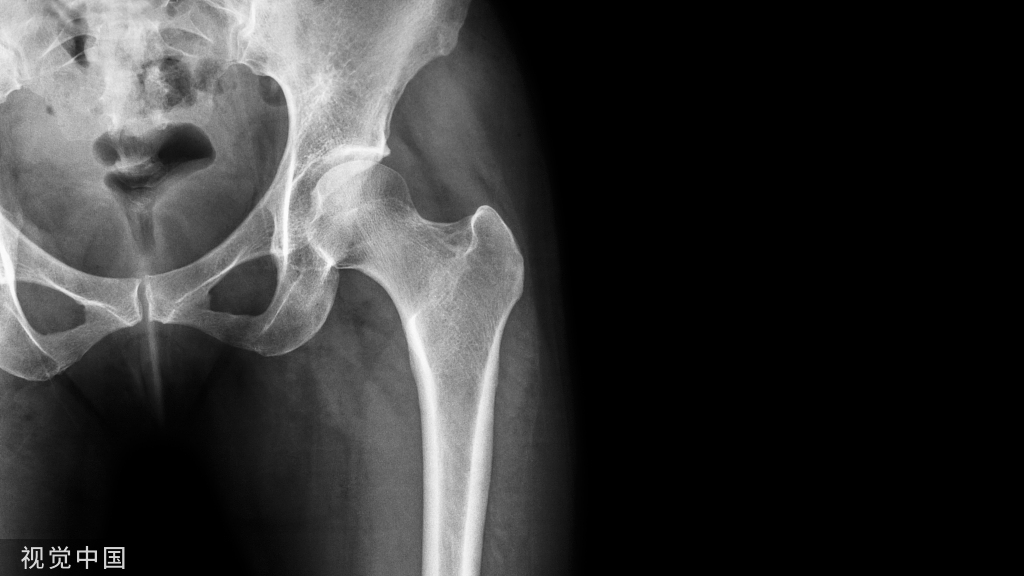

推荐意见2:对怀疑发生胸腰椎骨折的AS患者,因存在漏诊可能,不可行单纯X射线摄影进行排除性检查,推荐在X射线摄影检查的基础上同时行三维CT与MRI检查(推荐强度:3级)。

推荐意见3:不使用腰椎正位双能X线吸收测定法(DXA)评估骨质疏松情况,根据具体配备设备使用髋部DXA、定量CT(QCT)或骨小梁评分(TBS)进行评估(推荐强度:3级)。